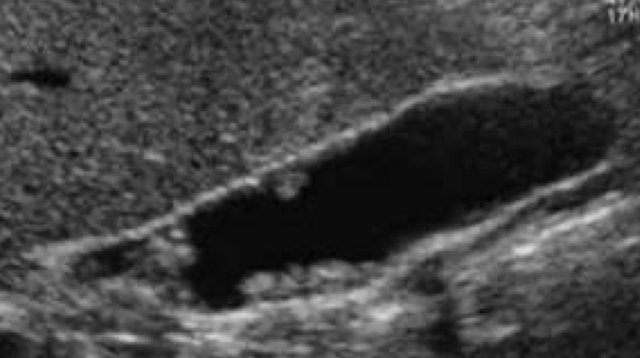

adenomyomatosis

cholesterol crystals that settle within the Rokitansky-Aschoff sinuses of GB wall

mucosal hyperplasia (thickening of muscular layer of GB wall); papillomas occur

SONO: thickening of wall with internal cystic spaces

echogenic foci on wall with “comet tail” artifact

??